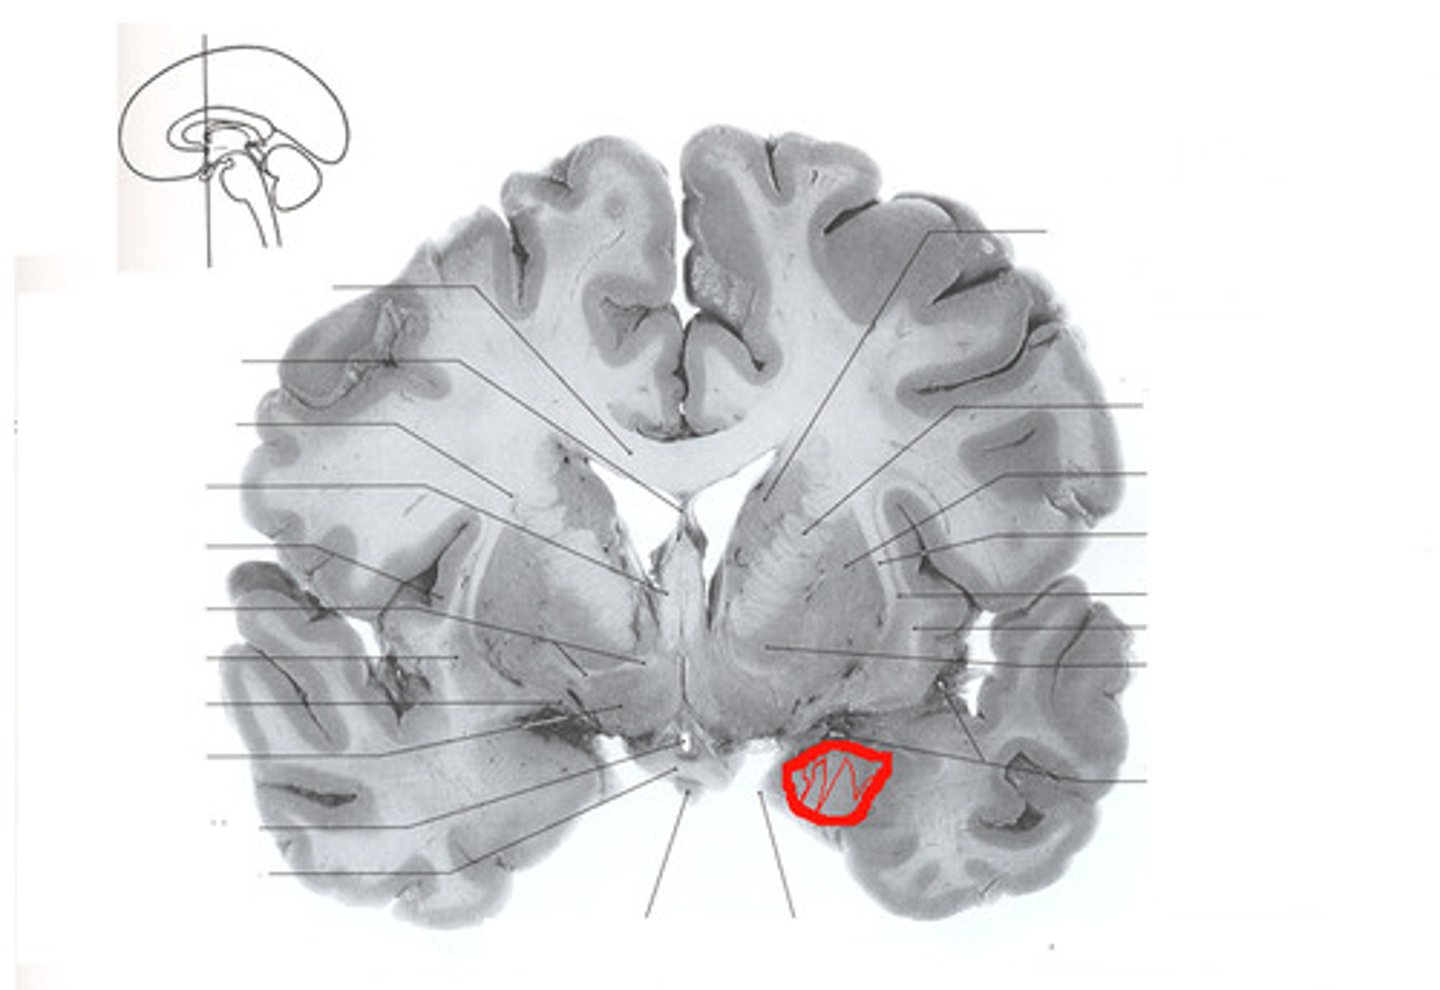

red nucleus

(red circle) - motor coordination

substantia nigra

globus pallidus

Putamen

subthalamic nucleus

a small nucleus, located ventral to the thalamus, that is part of the basal ganglia (anterior to red nucleus)

caudate nucleus - part of basal ganglia

lateral ventricles

3rd ventricle